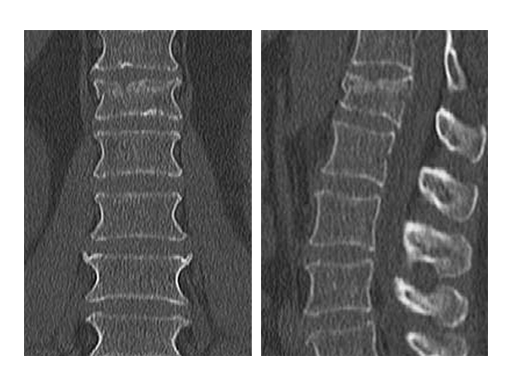

Preoperative analysis

X-rays and CT scans were performed for preoperative analysis, definition of the fracture type and surgical pre-op planning.

The lateral x-ray and CT scans showed a typical wedge deformity of the fractured vertebral body (L1). The fracture included the cranial endplate as well as the anterior and posterior wall.